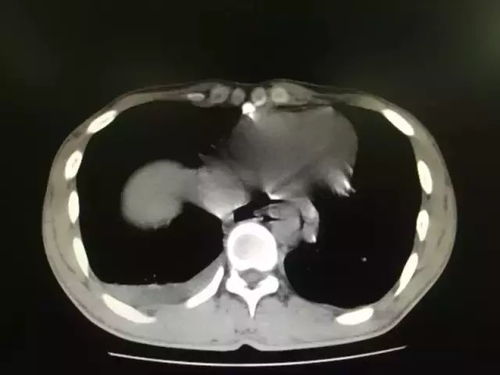

由于长时间专注于食物,张先生没有注意到自己的进食速度过快,当食物从口中滑落时,他的食道似乎承受不住巨大的压力,导致食管肌肉受到过度拉伸,最终出现裂缝,这个裂缝迅速扩大,直到最终贯穿食管壁,形成了一个长达几厘米的裂口。

张先生的情况虽然较为极端,但其引发的问题同样值得深思,食管穿孔是一种严重的医疗状况,可能引起一系列并发症,如感染、营养不良甚至生命危险,对于食管的修复,通常需要外科手术,恢复过程漫长且复杂。